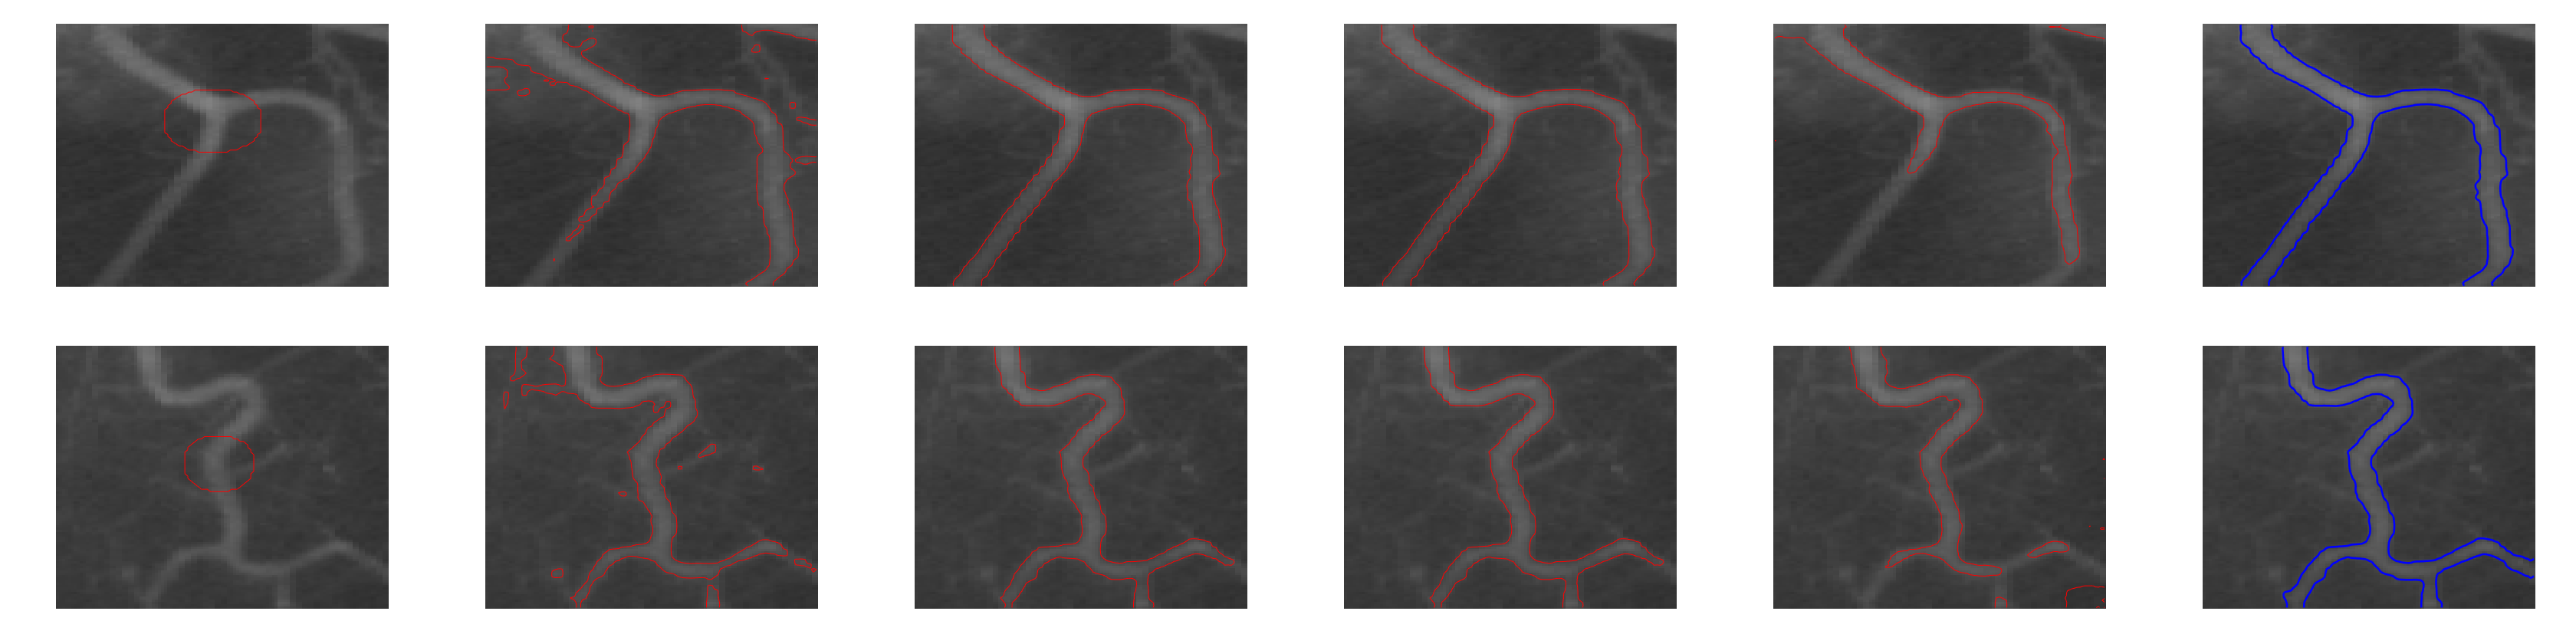

Similarly, Fig. (10) shows the segmentation results of two blood vessel images having intensity inhomogeneity and extremely weak boundaries. As global region based models, CV and SDREL are unable to segment the vessels from the background, whereas the local region based models such as the LBF and LIF models provide interesting results; however, the proposed model shows better results than all of the previous methods and segments the blood vessel with more accuracy and precision.